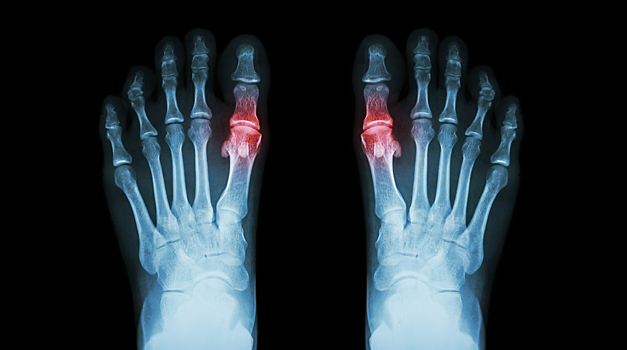

Подагра возникает, когда в крови повышается уровень мочевой кислоты, из которой образуются острые кристаллы. Они оседают в суставах, вызывая сильную боль, отёк и воспаление. Долгое время болезнь считалась результатом вредного образа жизни — переедания, злоупотребления алкоголем и малоподвижности. Однако ученые подчеркивают, что это ошибочное представление.

Исследователи сравнили ДНК 120 295 человек с подагрой и данных более 2,5 миллиона здоровых людей. В результате они выявили 377 участков генома, связанных с болезнью, из которых 149 ранее никогда не связывали с подагрой. Эти результаты подтверждают, что гены участвуют сразу в нескольких важных процессах: они влияют на способность организма выводить мочевую кислоту и определяют, насколько активно иммунная система реагирует на её кристаллы, вызывающие воспаление суставов.